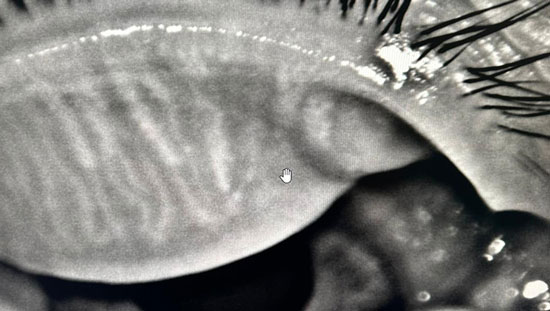

Non-invasive blepharoplasty

Blepharitis

Entropion

Acting on the cause rather than the symptoms

Towards targeted, sustainable treatment.

RF and IPL mainly rely on heat emission and gland expression to treat Meibomian Gland Dysfunction (MGD), stimulate collagen, and heat the Meibomian glands, Jett goes further. It also affects several other aspects of the ocular surface, influencing various mechanisms that contribute to dry eye and inflammatory conditions.

Jett technology directly stimulates the goblet cells responsible for mucin production, reducing excessive evaporation and contributing to better lubrication of the eye. It also supports the proper function of the orbicularis muscle to improve blink efficiency, which is essential for the even distribution of tears. By acting on the laxity of the lower eyelids and the Riolan muscle, it optimizes eyelid closure and tear distribution, thus reducing dryness.

Furthermore, with its new protocols, Jett stimulates the accessory lacrimal glands of Krause and Wolfring, which are responsible for producing the aqueous component of the tear film, promoting optimal aqueous secretion. It also strengthens local conjunctival immunity, an essential system for protecting the ocular surface. Finally, it acts on cell regeneration, improves meibum quality, and creates an astringent effect that enhances the function of the Meibomian glands. These combined mechanisms allow for a comprehensive, non-invasive management of dry eye and inflammation control.